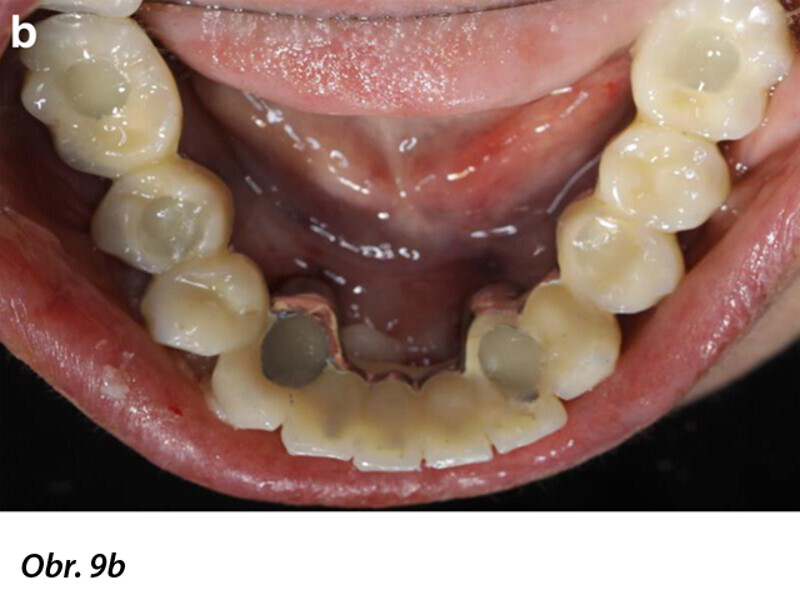

Počítačem asistované, šablonou se řídící okamžité zavedení a zatížení implantátu v dolní čelisti